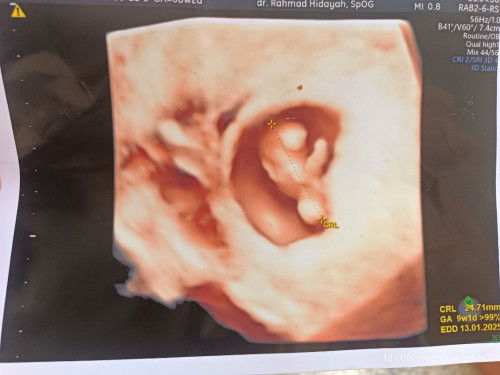

Kata dokter alhamdulillah sehatt,janinnya d dalam rahim,posisi bagus,detak jantungnya bagus juga#Sharing_dong_Bund 🤲,,stelah di vonis s bidan abal abal tu aku hamil d luar rahim😡

Bun pertama aku cek kehamilan aku tespack hasilnya positif dan aku langsung ke bidan untuk usg kehamilanku ini ,kata si bidan "iya ini hamil,hamilnya 6w3d"gitu katanya,langsung d vonisnya aku terkena hamil d luar rahim,ini tidka bisa d selmatkan,wlaupun dia berkembang nnti janinnya bisa pecah dan bisa menyebabkan pendarahan yg hebat,d situ aku sudah down mental ku bun😭dan hbis usg d kasihlah aku vitamin,suruh dtg 2 minggu lagi katanya,,,tapi d posisi ini aku bnar² sudah down bun,,aku berjanji nggak bakalan mw balik ke sini lagi,,dgn keyakinan aku aku dtglah k dokter d hari yg sma dan langsung masuk k ruangan usg dokte,,d sini aku terkejut apa kata si dokter ini🫣"alhamdulillah selamat ya bu,ibu hamil 4w6d,d sini dokter blg ini masih kantongnya y bu,trus oikiran aku masih terngiang² kata s bidan itu lalu ku tanyain lah,dok kantong janin nya d dalam apa d luar rahim? Lalu dokter jwb,,alhamdulillah ini didalam rahim kok bu,,bagus letak kantong dan posisinya,mmng dokter blg ini kandungannya lemah,tapi si dokter langsung kasih aku obat penguat dan vitamin asam folat,, Bagaimana pendapat moms,,ada yg pernah sama nggak sma aku lngsung d vonis yg nggak²🥺🥺#SeriusTanya #Sharing_dong_Bund #bantujawab #ingintahu #bantusharing